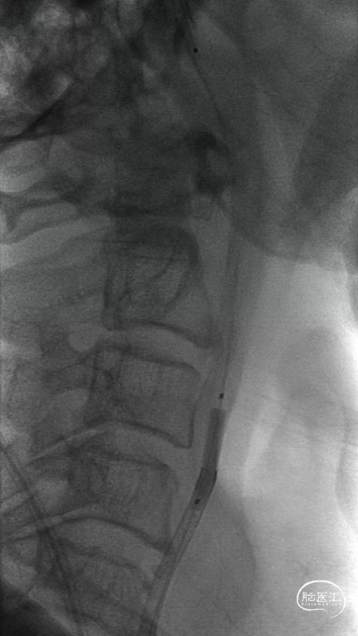

交换出微导管及多功能导管,C2段放置SPIDER保护伞后以3-30mm球囊和6F 115cm SKATHI远端通路导管采用球囊接力技术越过颈内动脉闭塞段,由下及上持续抽吸。

抽吸状态下整体撤出保护伞,继续抽吸,血栓堵塞SKATHI导管及导引导管,负压下整体将系统撤出,可见大量血栓。

微导管微导丝携SKATHI远端通路导管负压状态下再次进入颈内动脉,造影确认颈内动脉通畅,大脑中动脉中远段可见栓塞。

回撤SKATHI远端通路导管至C3段,通过导管再次释放SPIDER保护伞,回撤导管至颈总动脉,造影见C1段严重狭窄,以4-30mm球囊扩张狭窄段,复查造影狭窄段好转,远端再次闭塞,考虑斑块或血栓脱落,立即置入7-40 wallstent支架。